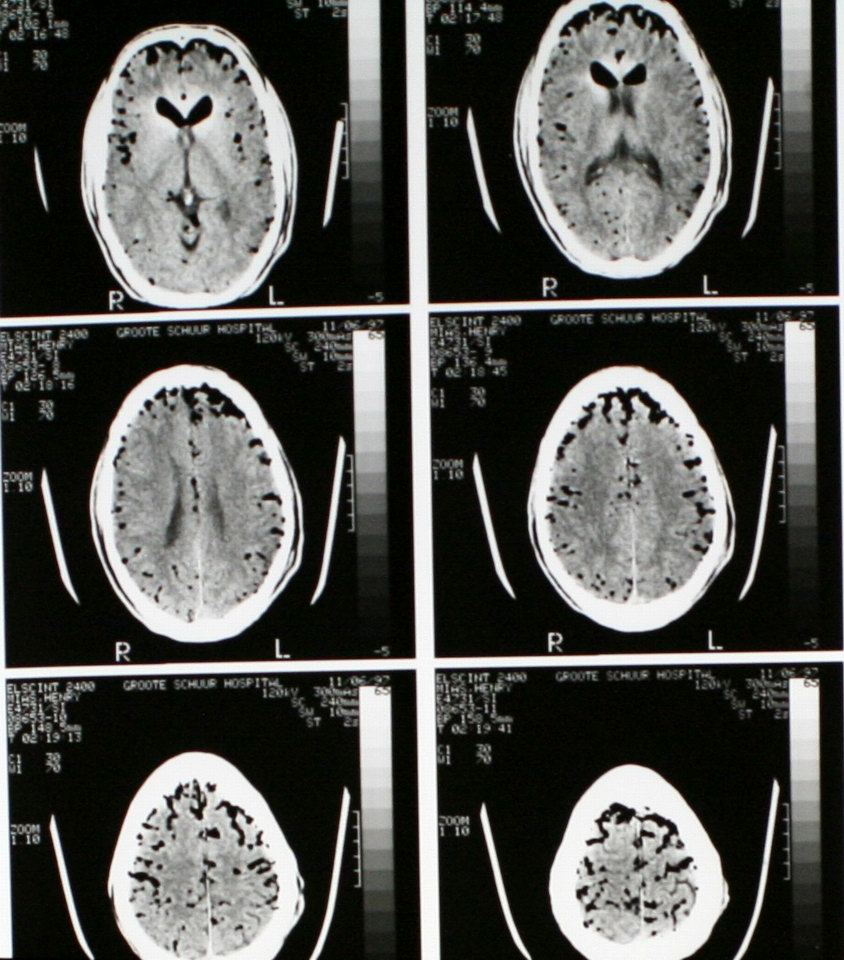

Air in the skull from a stabbing -- "pneumocranium" |

CT of same patient |